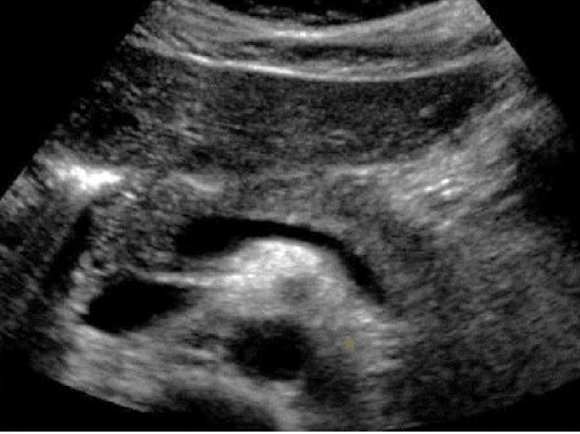

Look over this image

Which is shown in this image?

a longitudinal view of the CBD entering the pancreatic head. Pancreatic head outlined in orange